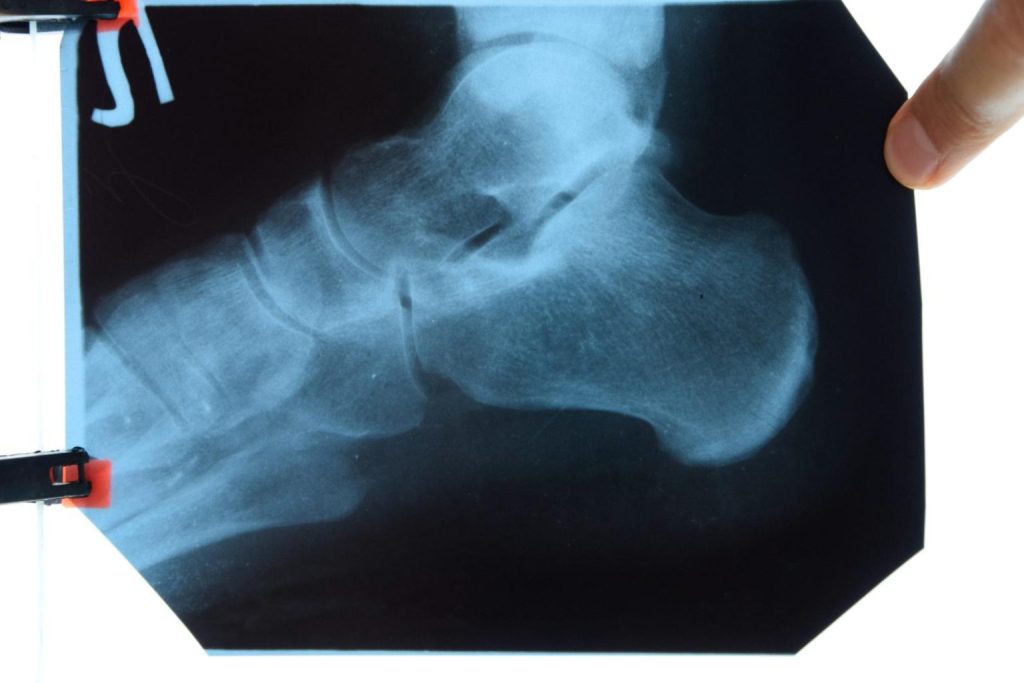

Introduction The heel is more than just the back part of your foot; it’s a complex structure comprising various bones, muscles, ligaments, and tendons. Understanding